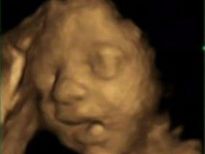

Bebeğin esneme anı

Bilim adamları bebeklerin ana karnındaki gelişimlerini daha iyi gözlemleyebilmek için ilginç bir deney yaptı. 15 anne adayının üzerine 4D ultrason sistemini kullanarak bebeklerin anne karnında ultrasonlarını çektiler. Çeşitli açılar ve teknikler kullanılarak yapılan bu yöntem normal ultrasonun aksine daha detaylı bir görüntü sağlıyor.